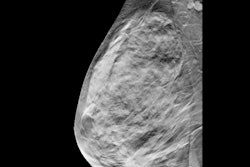

The prototype achieved a sensitivity of 97% and specificity of 60%. The radiologist reading the prototype images correctly identified 33 out of the 34 malignant lesions -- 26 visible on both DBT and ABUS, six only visible on DBT, and one only visible on ABUS.

The addition of ABUS helped the reading radiologist to better visualize cancers seen on DBT. With ABUS images, the radiologist correctly upgraded three cases of breast cancer -- two from BI-RADS 4B to 5 and one from BI-RADS 4A to 4B. In addition, ABUS identified invasive lobular carcinoma not seen on DBT.

The prototype also struggled with ABUS image quality. The reading radiologist rated most ABUS scans as having well-distinguishable tissue structures but a lower quality than handheld ultrasound. A total of 7% of lesions were also only partly visualized on ABUS and 11% were classified as BI-RADS 0 due to low image quality.